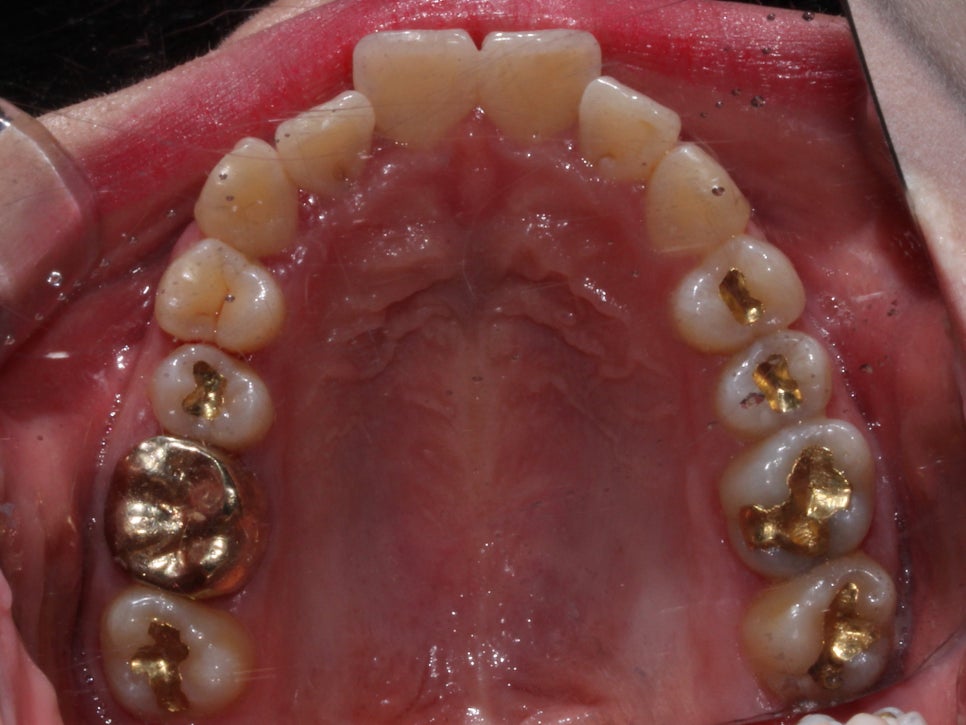

중간과정

우선 배열을 바로 잡기로 했습니다.

치아를 가지런하게 펴기 위해선

치간삭제는 필수적이었습니다.

삭제 없이 치아를 펴면

뻐드러지기 때문에

치아에 해를 끼치지 않는 선에서

치간삭제를 시행합니다.

꽤 많이 개선이 되었지만

아직 #12가 배열이 잘 되었다기 보단

그냥 거꾸로 물리던 것이 해소 된 정도입니다.

약간 뻐드러진 느낌과

치축만 조금 더 개선 시키고 마무리 하기로 했습니다.